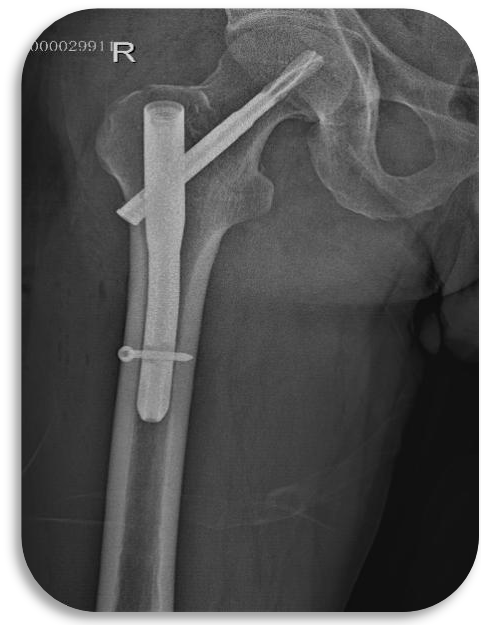

股骨近端骨折微创

股骨粗隆骨折髓内钉固定

股骨近端骨折髓内钉固定